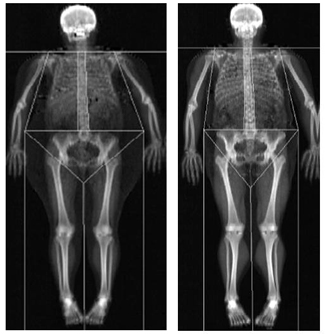

Recent researches on eating disorders state that the incidence of these disorders in men is fewer than in women, but serious doubts remain about the connection between the disorder and the gender of patients. Cases of anorexia nervosa in men have been studied, but...